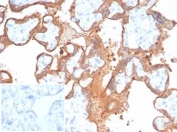

IHC staining of FFPE human placental tissue with recombinant Transglutaminase 2 antibody (clone TGM2/6943R). Negative control inset: PBS instead of primary antibody to control for secondary binding. HIER: boil tissue sections in pH 9 10mM Tris with 1mM EDTA for 20 min and allow to cool before testing.